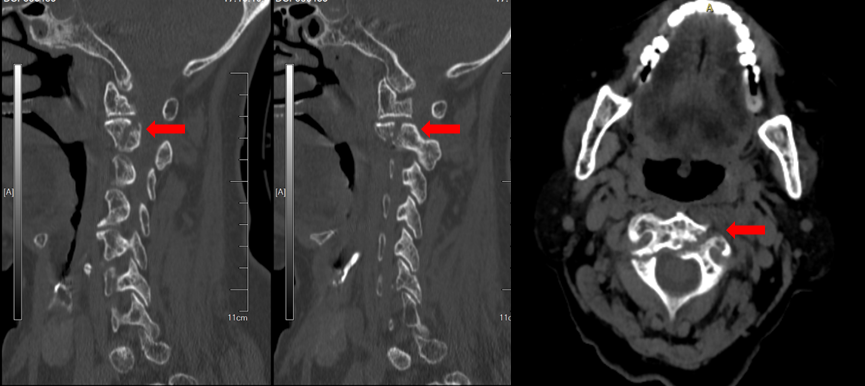

CT重建提示骨折同时合并一侧椎弓根先天性发育性狭窄